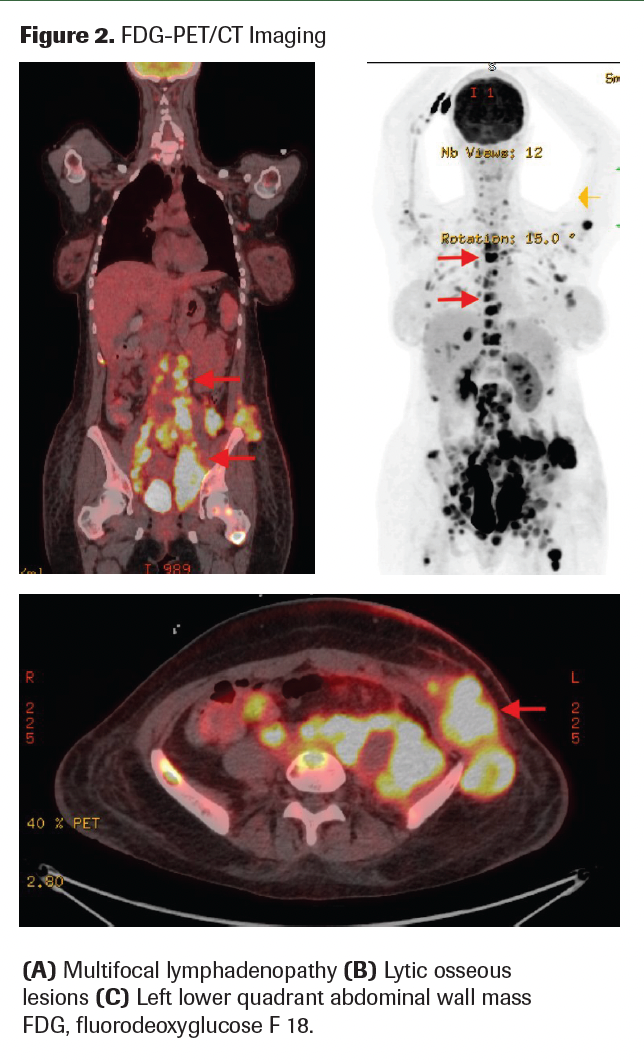

A fluorodeoxyglucose F 18 (FDG)–PET/CT scan revealed multifocal FDG-avid lymphadenopathy, lytic osseous lesions, and a left lower quadrant abdominal wall mass; overall radiographic findings were most suspicious for lymphoma (Figure 2). Hydronephrosis and left ovarian enlargement with mild FDG uptake were also noted, suggestive of a possible complex cyst rather than malignant involvement. An MRI of the brain revealed a right frontal bone lesion suspicious for metastasis but no intraparenchymal lesions.

Figure 2. FDG-PET/CT Imaging